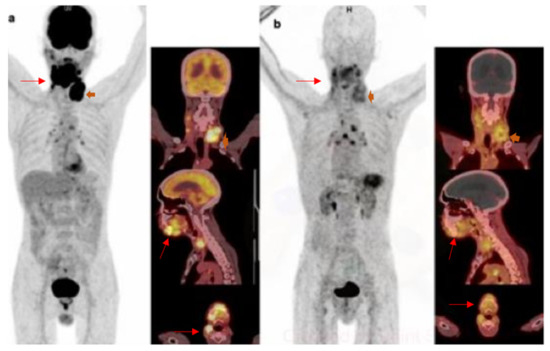

- Linde, P.; Baues, C.; Wegen, S.; Trommer, M.; Quaas, A.; Rosenbrock, J.; Celik, E.; Marnitz, S.; Bruns, C.J.; Fischer, T.; et al. Pentixafor PET/CT for imaging of chemokine receptor 4 expression in esophageal cancer—A first clinical approach. Cancer Imaging 2021, 21, 22. [Google Scholar] [CrossRef]

- Werner, R.A.; Weich, A.; Higuchi, T.; Schmid, J.S.; Schirbel, A.; Lassmann, M.; Wild, V.; Rudelius, M.; Kudlich, T.; Herrmann, K.; et al. Imaging of Chemokine Receptor 4 Expression in Neuroendocrine Tumors—A Triple Tracer Comparative Approach. Theranostics 2017, 7, 1489–1498. [Google Scholar] [CrossRef]

- Werner, R.A.; Kircher, S.; Higuchi, T.; Kircher, M.; Schirbel, A.; Wester, H.J.; Buck, A.K.; Pomper, M.G.; Rowe, S.P.; Lapa, C. CXCR4-Directed Imaging in Solid Tumors. Front. Oncol. 2019, 9, 770. [Google Scholar] [CrossRef]